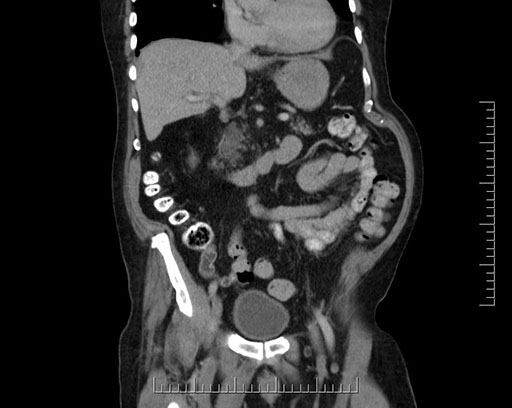

Whipple (pancreaticoduodenectomy) [case 7]

Imaging Analysis

Look through the patient's CT scan to identify any areas of concern for the necessary procedure.

Based on your CT findings, which issue(s) would give reason for "planned slowing down moment(s)" in this case?

Considering a standard Whipple procedure, what step(s) of the operation would you do differently in this case?